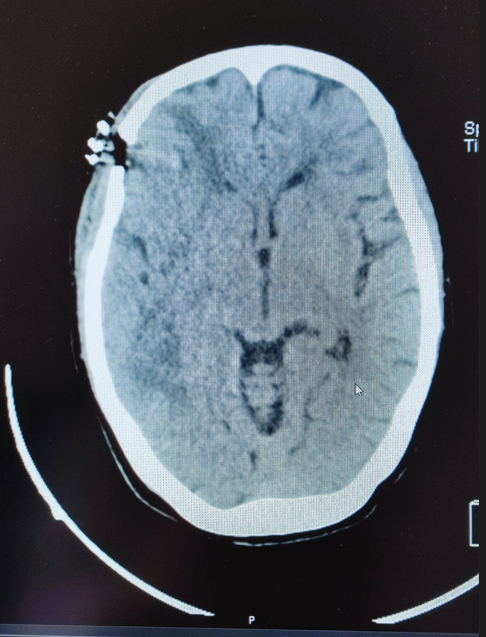

Cranioencephalic computed tomography revealed an expansile cortico-subcortical lesion predominantly centered in the right medial temporal lobe, with significant extension into the adjacent parietal and frontal lobes. The lesion demonstrated heterogeneous contrast enhancement and was surrounded by notable perilesional edema, contributing to local mass effect (Figure 1). A lumbar puncture was performed to analyze cerebrospinal fluid, effectively excluding infectious or lymphoproliferative causes.

Figure 1 Expansile temporal lesion with edema.